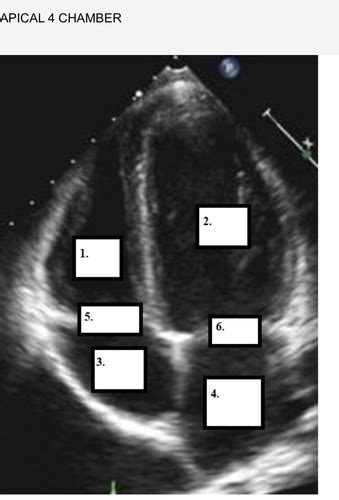

Alright team, let’s get down to the nitty-gritty of achieving that perfect apical view echo probe position . It might seem intimidating at first, but follow these steps, and you’ll be capturing stellar images in no time. First things first: patient positioning . The patient should ideally be lying on their left side, also known as the left lateral decubitus position. Why the left side, you ask? Because this rolls the heart towards the transducer, bringing the apex closer to the chest wall and minimizing the distance sound waves have to travel through lung tissue, which can scatter ultrasound signals. Ask the patient to bring their left arm up and over their head or rest it on a pillow. This helps to abduct the left arm and open up the intercostal spaces, giving you better access. Now, for the probe selection . Generally, a phased array transducer (the one with the small, curved footprint, often called a “cardiac probe”) is your best bet. Its shape allows it to get between the ribs easily. Now, where do we place the probe? We’re looking for the apical impulse or point of maximal impulse (PMI) , which is usually felt in the 5th or 6th intercostal space at the mid-clavicular line. You might need to palpate the chest to find this spot. Once you’ve found a likely area, apply a good amount of ultrasound gel – don’t be shy with the gel, guys! It’s essential for good sound transmission. Place the probe perpendicular to the chest wall initially. The probe marker (usually a dot or a line) should be pointing towards the patient’s right shoulder or slightly towards the head. Now, here comes the art: manipulating the probe . Start with a standard apical four-chamber view. You’ll want to fan the probe slightly up and down, side to side, and rock it gently to optimize the image. Think of it like gently sweeping the probe across the area. The goal is to see all four chambers clearly: the left atrium, left ventricle, right atrium, and right ventricle. The left ventricle should be the largest chamber, and you should clearly visualize the mitral valve between the left atrium and left ventricle, and the tricuspid valve between the right atrium and right ventricle. Depth and gain adjustments are also critical. You might need to adjust the depth to ensure the entire heart is in the field of view, and the gain controls help to brighten or darken different parts of the image to make structures more visible. Common adjustments include decreasing the depth and increasing the gain as you get closer to the apex. If you’re having trouble seeing the apex clearly, try moving the probe slightly inferiorly and medially. Sometimes, a slight tilt of the transducer can bring the apex into better view. Remember, patience is key! You might need to try a few different spots and angles. The key takeaway here is left lateral decubitus position , finding the PMI, and then gently fanning and tilting the transducer to achieve optimal visualization of all four chambers and the valves. We’re aiming for that iconic image where the left ventricle looks like a bullet pointing towards the transducer. It’s all about finding that sweet spot where the heart is presenting its best profile to the sound waves. Keep practicing these steps, and you’ll master the apical view in no time, I promise! It’s a journey, but a very rewarding one.

Now that we’ve got the basics of positioning down, let’s talk about really optimizing the apical view echo probe position , specifically the apical four-chamber view. This is arguably the most important apical view, and getting it right means you’re well on your way to a diagnostic echocardiogram. When we talk about optimization, we’re aiming for clarity, completeness, and accuracy. First off, probe orientation is key. Remember we placed the marker pointing towards the patient’s right shoulder for the standard view? To optimize, you might need to slightly adjust this. Think of the probe as having two axes: the long axis (up-down) and the short axis (side-to-side) relative to its footprint. Gently rocking the probe from heel to toe (or toe to heel) helps you see different parts of the heart. Fanning the probe up and down, like opening a book, allows you to sweep through the heart and ensure you’re not missing any structures. You’re looking for a symmetrical appearance of the ventricles and atria, with the interventricular septum and the interatrial septum appearing as thin, distinct lines. Mitral valve visualization is paramount here. You want to see both the anterior and posterior leaflets of the mitral valve clearly opening and closing. If one leaflet seems foreshortened or obscured, try adjusting your probe angle slightly. Sometimes, tilting the probe away from the septum can bring the mitral valve into better view. Similarly, for the tricuspid valve , you want to see its leaflets. It might be slightly less prominent than the mitral valve in this view, but its function is just as important. Symmetry and Proportions are your visual cues for a good four-chamber view. The left ventricle should appear larger than the right ventricle. The atria should also be clearly delineated. If the ventricles look unusually shaped or disproportionate, you might be slightly off-axis, and adjustments are needed. Aortic and Pulmonary Artery Visualization are secondary goals in the four-chamber view but can sometimes be glimpsed. You might see a sliver of the aortic outflow tract posterior to the left atrium, and the pulmonary artery may be seen superiorly. If you need to specifically assess these, you’d move to other views, but their partial visualization here can be helpful for orientation. Doppler Integration is where this view really shines for functional assessment. Placing spectral Doppler on the mitral inflow allows you to assess diastolic function (E-wave and A-wave velocities). Color Doppler across the mitral valve helps identify any regurgitation. Similarly, Doppler on the tricuspid inflow and valve can provide information about right heart function and tricuspid regurgitation. Patient Factors also play a role in optimization. If you have significant lung overinflation (common in COPD patients), you might need to try positioning the patient slightly more upright or even on their right side for a brief moment to see if that improves visualization, though the left lateral decubitus is still preferred. Obesity can also make it harder to reach the apex, requiring deeper penetration and potentially lower-frequency transducers. Don’t be afraid to adjust gain and depth settings dynamically. As you fan through the heart, the optimal settings will change. Many modern machines have automatic gain control (AGC) features, but manual adjustments often yield superior results. The ultimate goal of optimization is to obtain a view that is not only anatomically correct but also allows for accurate functional assessment. This means clear visualization of all four chambers, the interatrial and interventricular septa, and all four valves (mitral and tricuspid are best seen here). So, keep fanning, keep rocking, adjust your depth and gain, and don’t be afraid to make small, precise adjustments. You’re aiming for that textbook image, guys! It takes practice, but the payoff in diagnostic accuracy is immense.